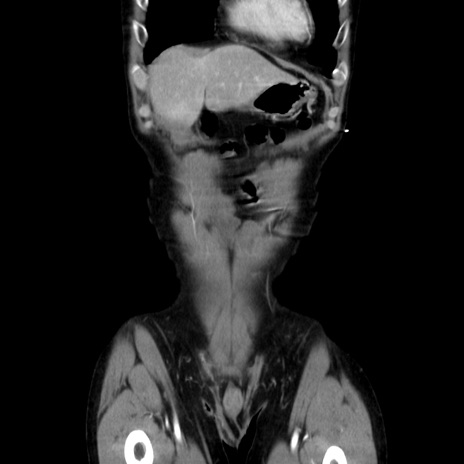

症例37(冠状断像)

【症例】40歳代 男性

【主訴】腹痛

【現病歴】4時間ほど前に電車に乗車中に臍部上より腹痛出現。徐々に増悪し起立困難となり、救急外来受診。生ものは数日食べていない。今朝お雑煮を食べた。

【身体所見】BT 36.8℃、BP 117/84mmHg、HR 91/min、SpO2 97%、苦悶様、腹部:臍上部広範囲圧痛あり、反跳痛±

【データ】WBC 8100、CRP 0.03